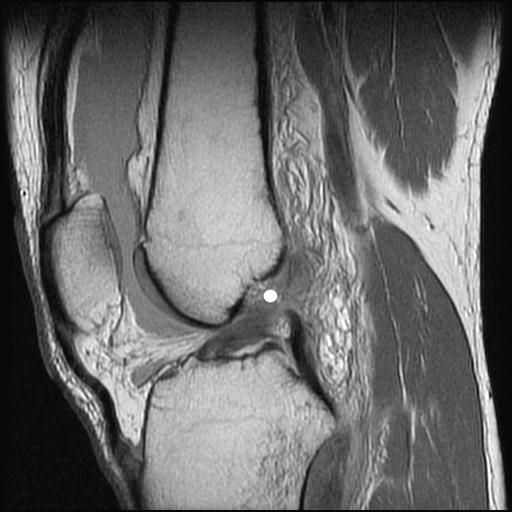

Magnetresonanztomographie (Kernspintomographie) eines vorderen Kreuzbandrisses (mit weissem Punkt markiert)

Der Riss des vorderen Kreuzbandbandes (VKB–Ruptur) gehört zu den häufigsten Bandverletzungen des Menschen. Studien geben eine Häufigkeit von einer VKB-Ruptur pro Jahr und pro 1000 Einwohner an. Das vordere Kreuzband zählt zusammen mit dem hinteren Kreuzband, dem Innen- und Außenband und den Menisken zu den Stabilisatoren des Kniegelenkes und ist selbst der wichtigste Stabilisator. Das vordere Kreuzband ist ein ca. 2 cm langes und etwa kleinfingerdickes Faserbündel, das zentral im Kniegelenk vom Schienbeinkopf zum Oberschenkelknochen zieht. Die Diagnose einer Kreuzbandruptur kann normalerweise anhand der Anamnese und einer eingehenden klinischen Untersuchung gestellt werden. Gesichert wird die Diagnose durch eine Kernspintomographie (MRT) . Beim Riss des vorderen Kreuzbandes kommt es zur Ausbildung einer Instabilität des Kniegelenkes. Die Gelenkfunktion ändert sich und die übrigen Stabilisatoren des Gelenkes werden zusätzlich belastet. Durch den Verlust des vorderen Kreuzbandes kommt es insbesondere bei unbewussten, muskulär nicht kontrollierten Bewegungen zum typischen Wegknicken mit Herausrutschen des Unterschenkels (sogenanntes Giving way). Wiederholtes Wegknicken kann im Laufe der Zeit zur Auslockerung des Kapsel-Band-Apparates und so zu einer chronischen Knieinstabilität führen. Zusätzlich können Meniskusrisse und Knorpelschäden an den Oberschenkelrollen entstehen. Eine rein muskuläre Stabilisierung der vorderen Kreuzbandinsuffizienz ist nicht vollständig möglich.